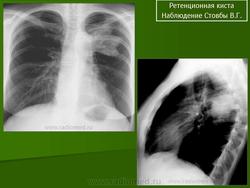

Ретенционная киста. Чт, 11/08/2011 - 20:34 #1 Nikolas Не на сайте Был на сайте: 1 месяц 1 неделя назад Зарегистрирован: 21.12.2010 - 20:37 Публикации: 4560 бронхиальной кисты не наблюдал. Спасибо за наблюдение. С уважением Nikolas Пт, 13/04/2018 - 22:06 #2 Миргалина Не на сайте Был на сайте: 1 месяц 5 дней назад Зарегистрирован: 06.08.2015 - 20:04 Публикации: 2882 Nikolas wrote: бронхиальной кисты не наблюдал. Спасибо за наблюдение. С уважением Nikolas Really? А какие Вы наблюдали?